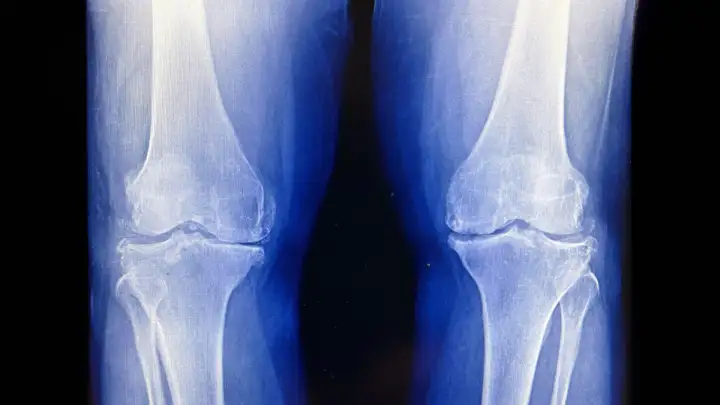

Результаты нового клинического исследования, проведенного Медицинским колледжем Сеульского национального университета (Южная Корея), показали, что однократный курс низкодозной лучевой терапии может облегчить боль и улучшить функцию сустава у пациентов. В исследовании приняли участие 114 пациентов, у которых был диагностирован умеренный остеоартрит коленного сустава, выявленный на рентгеновских снимках.